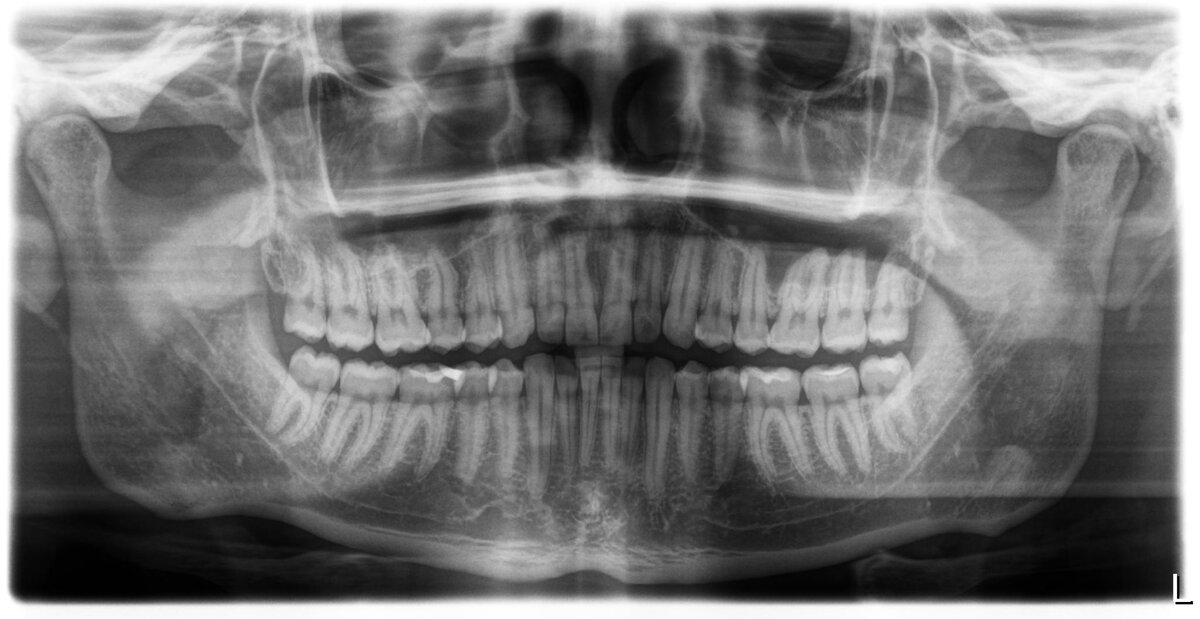

Зубы мудрости, или восьмерки, есть в разном количестве почти у каждого нашего пациента, у кого-то они почти не вызывают неприятностей, а у кого-то мы видим такую картину:

Например у этого пациента все четыре зуба мудрости прорезались правильно и даже в полости рта стоят ровно